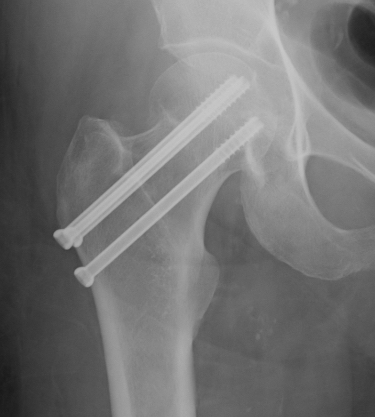

Cannulated screws

Technique

Lateral on traction table

- adequate reduction / no varus

- small incision or percutaneous

- 3 screws

- ensure inferior screw entry point is above lesser trochanter to prevent fracture

- ensure threads cross fracture site entirely to obtain compression

- need correct screw length so screw head can compress against cortex